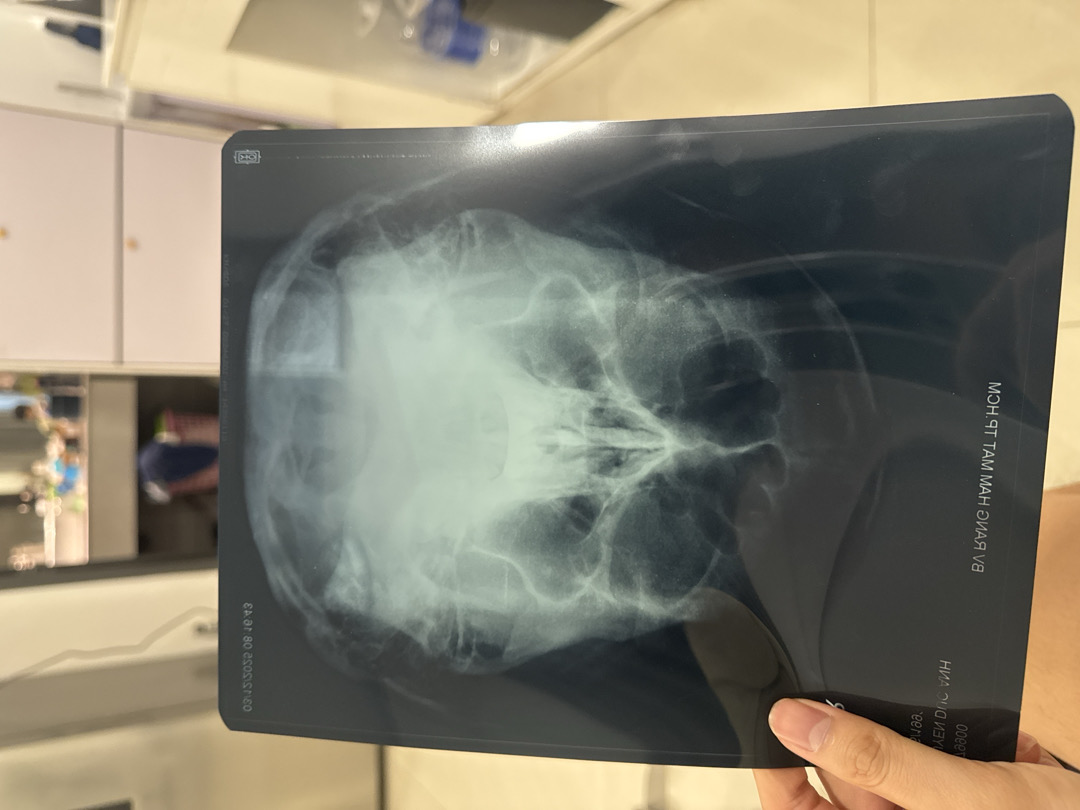

Cách đây 1 tháng rưỡi em có phẫu thuật nâng mũi khẩu hay gọi là nang ống mũi tại bệnh viện răng hàm mặt. Sau mổ thì vết thương lành tốt tuy nhiên là em luôn có cảm giác bị đau đầu nặng mặt, trán và nặng 2 bên cánh mũi. Sau khi tái khám bệnh viện răng hàm mặt thì bác sĩ có cho chụp X quang xoang hàm và kêu em khám thêm chuyên khoa tai mũi họng